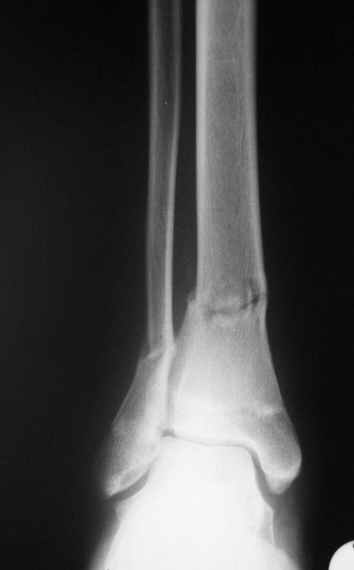

Уважаемые коллеги,Больной 17 лет , 3 недели с момента травмы, был переведен в наше отделение из соседнегогоспиталя.

Попытка закрытой ручной репозиции, предпринятая ранее в этой больнице,оказалась безуспешной, что и явилось причиной перевода к нам.Чтобы вы предложили в данной ситуации?Показана ли фиксация перелома малоберцовой кости в данном случае или в этом нет необходимости?Евгений Чекашкин

Консолидация перелома в указанной зоне у больных молодого возраста происходит довольно-таки быстро - уже через 3 недели определялись едва заметные качательные движения.

соответственно попытка улучшить стояние отломков закрытой манипуляцией оказалась безуспешной.

На прямой проекции видно угловое смещение отломков малоберцовой кости, обуславливающий и

наклон тарана, да и вальгус отломков б.б. , а на боковой проекции -смещение отломков

кпереди и по длине.

Коррекция углового смещения и смещения по длине отломков м.б. кости автоматом устраняет

наклон тарана , что необходимо для нормальной функции голеностопа. Так оно и произошло во

время операции.